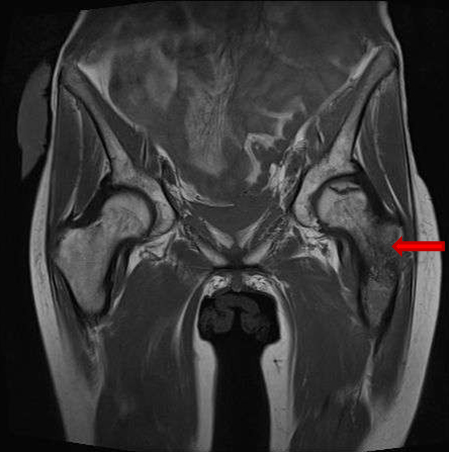

She presented on Emergency room suffering from fever, pelvic pain, and functional impairment of her right lower limb. Physical examination revealed bad smell vaginal flow and loss of strength on her right lower limb. Contrast computerized tomography and magnetic resonance images showed pelvic muscles impairment (Figure 1), inflamed bladder (Figure 2), and pelvic abscess lying from right psoas muscle to pubis bone, which presented radiologic signs of osteomyelitis (Figure 3) and (Figure 4).

Figure 9: MR image. Left femoral head avascular necrosis. Left femoral diaphysis severe impairment, affecting around 200 mm, with aheterogeneous morphology, with cortical disruption and moderate edema on adjacent muscles.

Share Image: